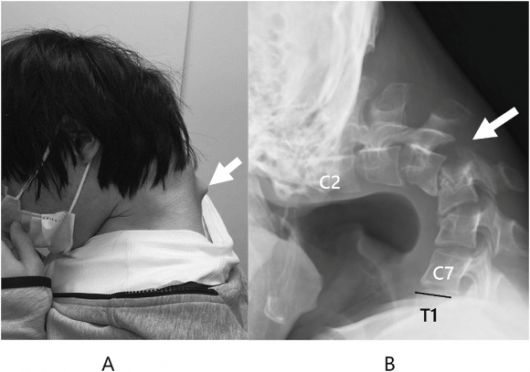

환자의 목에서 뿔처럼 솟아오르는 혹에 대해 의료진은 환자의 척추가 장기간의 부자연스러운 자세로 인해 ‘매우 확장’된 것으로 추정했다. 일본정형외과 학회지(JOS)의 사례 연구집 논문 캡처 |

거의 ‘ㄱ’자 형태로 심하게 꺾인 목, 뿔처럼 튀어나온 목뼈.

일본 규슈 오이타현의 오이타 정형외과를 찾은 남성 환자(당시 25세)는 한눈에 봐도 그 상태가 심각했다.

환자는 병원을 찾기 전 6개월 동안 심한 목 통증을 겪고 있었으며 고개를 들어 올릴 수 없다고 호소했다. 목이 너무 심하게 꺾여 그의 턱은 가슴에 거의 맞닿아 있었다.

이 환자의 심각한 경추 후만증과 ‘머리떨굼증후군’의 직접적인 원인은 좋지 않은 자세로 스마트폰을 과다 사용했기 때문으로 진단됐다. 목을 깊이 구부리고 스마트폰을 내려다보는 습관이 오랜 기간 지속되면서 척추에 악영향을 끼쳤다는 것이다.

환자의 척추가 장기간의 부자연스러운 자세로 인해 크게 변형된 모습. 일본정형외과 학회지(JOS)의 사례 연구집 논문 캡처 |

정밀검사를 진행한 결과 목뼈가 왜곡되고 탈구됐으며, 시간이 지나면서 척추(특히 경막) 부위에 흉터 같은 조직이 증식한 것이 관찰됐다.